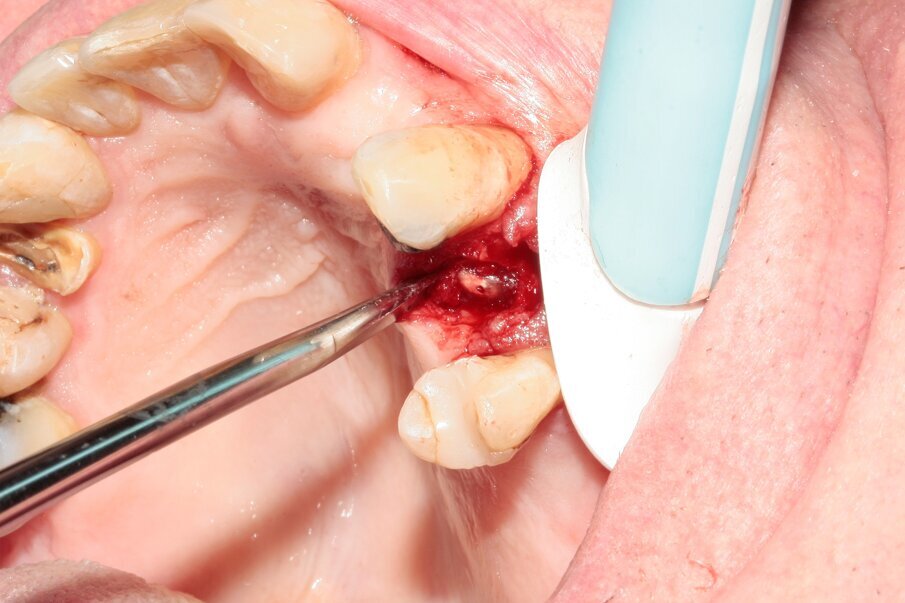

A 70-year-old female patient visited our clinic owing to a fractured maxillary first molar. Tooth #24 had previously had a large composite restoration that was no longer in place at the time of the dental appointment.

Tooth #24 was severely decayed down to the marginal bone edge.

Figs. 2–4: The tooth was luxated with Luxator P4 (dual edge, lilac).

Figs. 5–7: Luxation was continued with Luxator P1 (straight blade, dark green).